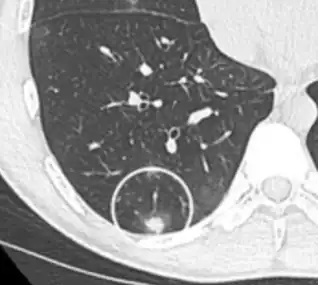

CT image showing ground-glass opacification in the posterior of the right lung (screen left). - Measles

CT image showing ground-glass nodule (circled).